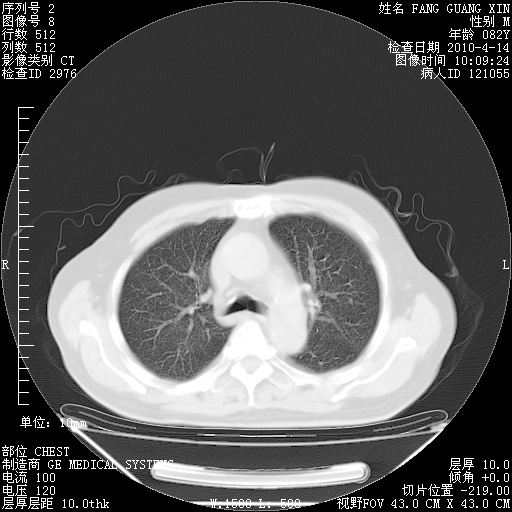

4月14日肺部CT

23.JPG

24.JPG

25.JPG

26.JPG

肺部CT平扫未见异常。